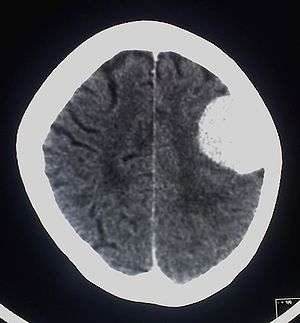

| A contrast-enhanced CT scan of the brain, demonstrating the appearance of a meningioma | |

The investigations completed at the Eberhard Karls University of Tuebingen in 2003 by Alfred Czarnetzki, Carsten M. Pusch and Erwin Schwaderer, showed that the owner of the skull suffered from a meningioma, which is an arachnoid tumor.[7] Meningiomas are a diverse set of tumors that arise from the meninges, which is the membranous layers surrounding the central nervous system.[8]

The slow-growing tumor was the size of 51 mm x 43 mm x 25 mm and a volume of 29 ml (1 imp fl oz; 1 US fl oz). It is believed that this tumor may have caused headaches. It is also possible that no neurological deficiencies were suffered, due to the slow growing nature of meningiomas.[7] Whether the tumor should be considered the cause of death cannot be determined from the remains. Having the rest of the skeleton would be necessary for further investigation into a possible cause of death. Meningiomas are very rare with roughly 2 out of 100,000 causing symptoms, so finding evidence of one in such ancient remains is a very exciting discovery.[9] It is the earliest evidence of a meningioma tumor on record.